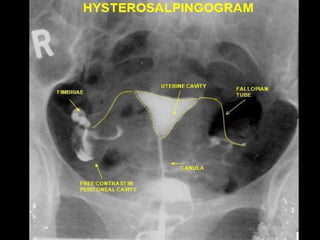

– Hysterosalpingography

Imaging Modalities forthe Abdomen and Pelvis. • Commonly utilized: • Ultrasound • CT (computed tomography) • Radiography • Abdominal plain film • Fluoroscopy – Hysterosalpingography • Other modalities: • MRI – Magnetic resonance imaging • Nuclear medicine – Gallium scan • Positron Emission Tomography (PET).